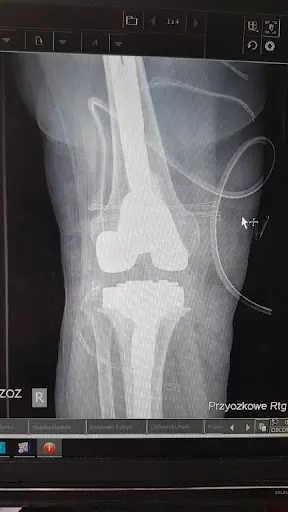

### Lek. Emil Rybaczek – ortopeda z Gdyni ceniony przez pacjentów W sercu Gdyni, przy ulicy Mikołaja Kopernika 38/5, przyjmuje lek. Emil Rybaczek, specjalista ortopedii. Gabinet w dzielnicy oznaczony kodem pocztowym 81-411 cieszy się wysoką oceną 4.8 na 5 w Google, opartą na 16 opiniach pacjentów. To miejsce, gdzie pacjenci z problemami układu ruchu – od bólu kolan po złamania kostek czy bioder – znajdują fachową pomoc, często w ramach NFZ. Doktor Rybaczek prowadzi zarówno diagnostykę, jak i zabiegi operacyjne, takie jak rekonstrukcja ACL, artroskopia kolana czy operacje kostki. Pacjenci podkreślają trafność diagnoz i profesjonalizm doktora. Wielu chwali szybkie decyzje terapeutyczne, staranne wykonanie zabiegów oraz wzorową opiekę pooperacyjną w przychodni. „Doktor przejął się moim problemem, wyjaśnił wszystko szczegółowo i konkretnie” – piszą w opiniach, doceniając komunikację, empatię i zaangażowanie. Mimo jednej negatywnej recenzji, dominują głosy o miłym kontakcie z lekarzem, który słucha pacjentów i traktuje ich z szacunkiem. Wielu poleca specjalistę znajomym, zaznaczając sprawny przebieg wizyt i brak długich opóźnień. Lek. Emil Rybaczek to ortopeda, na którego warto zwrócić uwagę w Trójmieście. Jego praktyka przywraca zaufanie do lokalnej służby zdrowia, łącząc wiedzę medyczną z życzliwością wobec pacjentów. (198 słów)